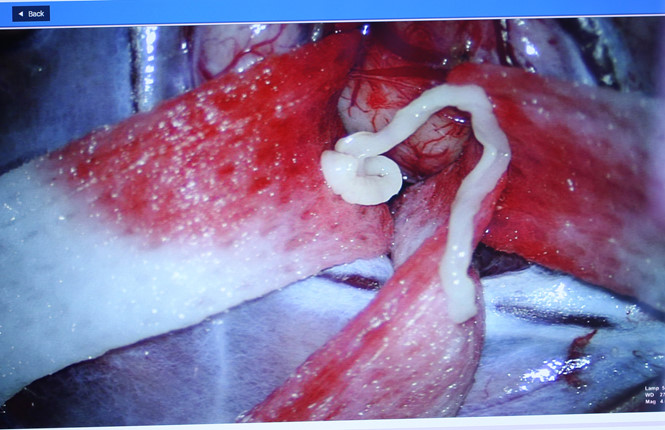

Mới đây các bác sĩ đã cứu 1 nạn nhân thành công sau khi lấy ký sinh trùng dài 7cm ra khỏi não. Được biết trước đó bệnh nhân này bị đau đầu và co giật. Dưới đây là 1 số thông tin đáng chú ý về vụ việc. Bệnh nhân đến bệnh viện khám do đau đầu, yếu nửa người kèm co giật. Các bác sĩ phẫu thuật đã phát hiện và lấy từ trong não bệnh nhân ra kí sinh trùng dài 7 cm.Ngày 20.12, tiến sĩ - bác sĩ Nguyễn Minh Anh, Trưởng khoa Ngoại Thần kinh, Bệnh viện Đại học Y dược TP.HCM (BV ĐHYD), cho biết: anh N.N.A (52 tuổi, ngụ Lâm Đồng) đến khám với những triệu chứng đau đầu, yếu nửa người kèm co giật.

Sau khi người bệnh được thăm khám và thực hiện chụp cộng hưởng từ sọ não, các bác sĩ chẩn đoán anh A. có tổn thương choán chỗ vùng vỏ não vận động có thể do u hoặc nang kí sinh trùng trong não.Khi ca phẫu thuật được thực hiện, các bác sĩ đã xác định chính xác bệnh lý của anh A. là u nang kí sinh trùng trong não.

Các bác sĩ đã lấy được kí sinh trùng dài khoảng 7 cm trong não người bệnh.

Kết quả giải phẫu bệnh cho thấy đây là loại kí sinh trùng có tên khoa học là Spirometra erinaceieuropaei hay còn gọi là sán nhái.

Bác sĩ Minh Anh cho biết: Người dân có nguy cơ nhiễm kí sinh trùng này khi ăn thịt ếch, nhái, gà, vịt, chim không nấu chín kỹ.Sán nhái thường kí sinh ở mắt người, rất hiếm khi có ở não.

Theo tiến sĩ - bác sĩ Nguyễn Minh Anh, Trưởng khoa Ngoại Thần kinh, BV ĐHYD, khó khăn lớn nhất trong ca phẫu thuật này là vị trí mổ nằm ở vùng vỏ não vận động.

Chức năng vận động của con người được điều khiển bởi vỏ não vận động và các bó dẫn truyền. Khi phẫu thuật thần kinh sẽ có nguy cơ làm tổn thương vùng vỏ não vận động này, dẫn đến ảnh hưởng đến chức năng vận động, khiến người bệnh liệt nửa người không hồi phục.

Ê kíp mổ BV ĐHYD đã sử dụng hệ thống máy theo dõi điện sinh lý thần kinh trong phẫu thuật sọ não và cột sống để giúp giảm thiểu nguy cơ tổn thương trong quá trình phẫu thuật cho người bệnh.